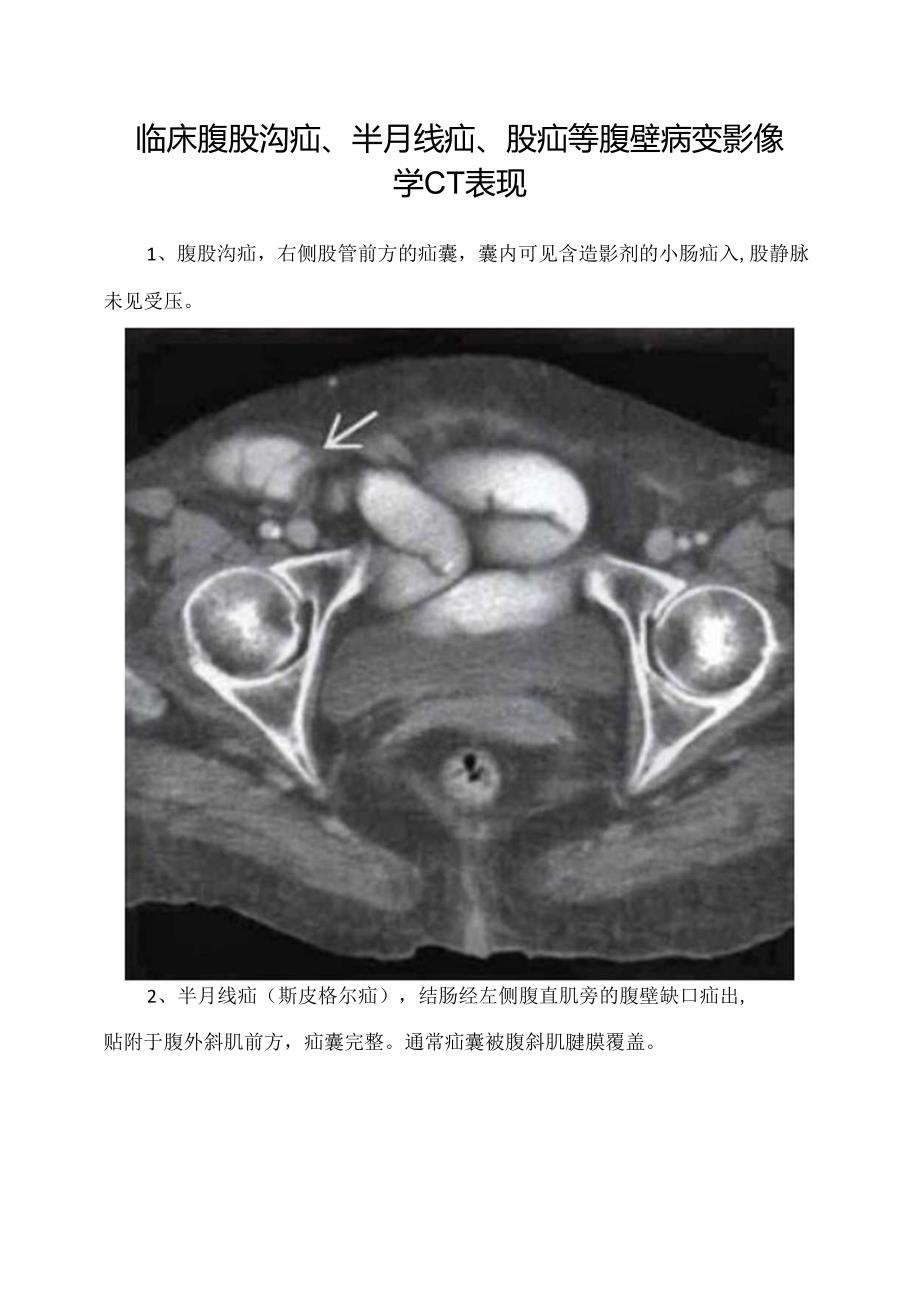

1、临床腹股沟疝、半月线疝、股疝等腹壁病变影像学CT表现1、腹股沟疝,右侧股管前方的疝囊,囊内可见含造影剂的小肠疝入,股静脉未见受压。2、半月线疝(斯皮格尔疝),结肠经左侧腹直肌旁的腹壁缺口疝出,贴附于腹外斜肌前方,疝囊完整。通常疝囊被腹斜肌腱膜覆盖。3、股疝,疝囊位于左侧耻骨结节与股静脉中间,疝入的小肠有梗阻。4、腰疝,CT表现见脂肪和小肠经左能崎附近的胸腰筋膜缺口疝出。5、皮脂腺囊肿,右臀部一包膜完整、水样密度病灶。6、腹壁血肿患者,右前下腹壁连接腹腔的透析导管,周围可见-闭块状高密度病灶。7、r宫内膜异位症,该病例为经历剖腹产的患者,腹壁切口周围一团块状软组织密度病灶,病灶部位周期性疼痛。8